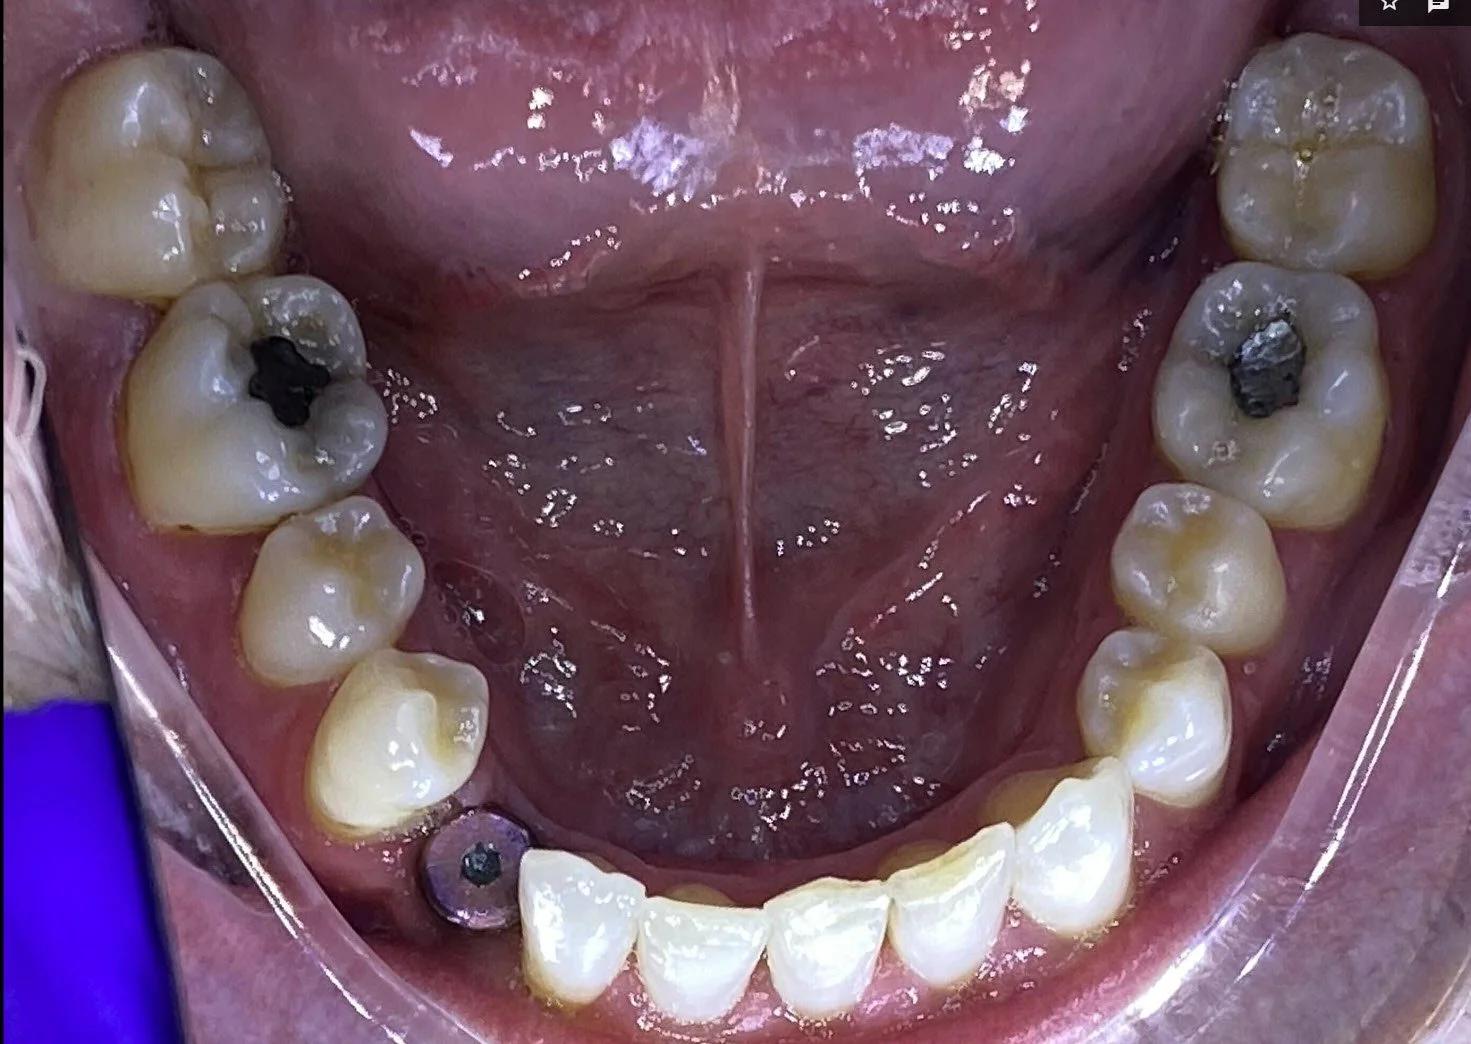

Before